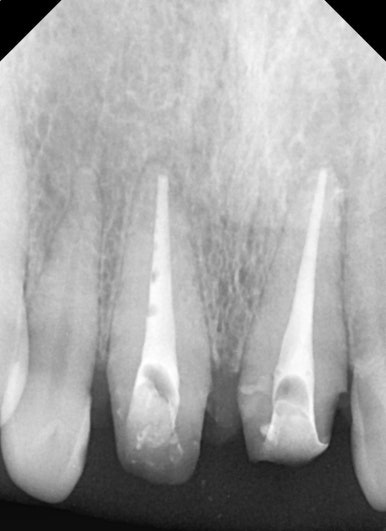

엑스레이 검사 결과, 뿌리 끝에는 염증도 생겨 있었습니다.

단순히 겉모습의 문제만이 아니라, 치아 뿌리 쪽도 치료가 필요했던 상황이었습니다.

25.08.11

25.08.11 기존 크라운 제거 후 모습